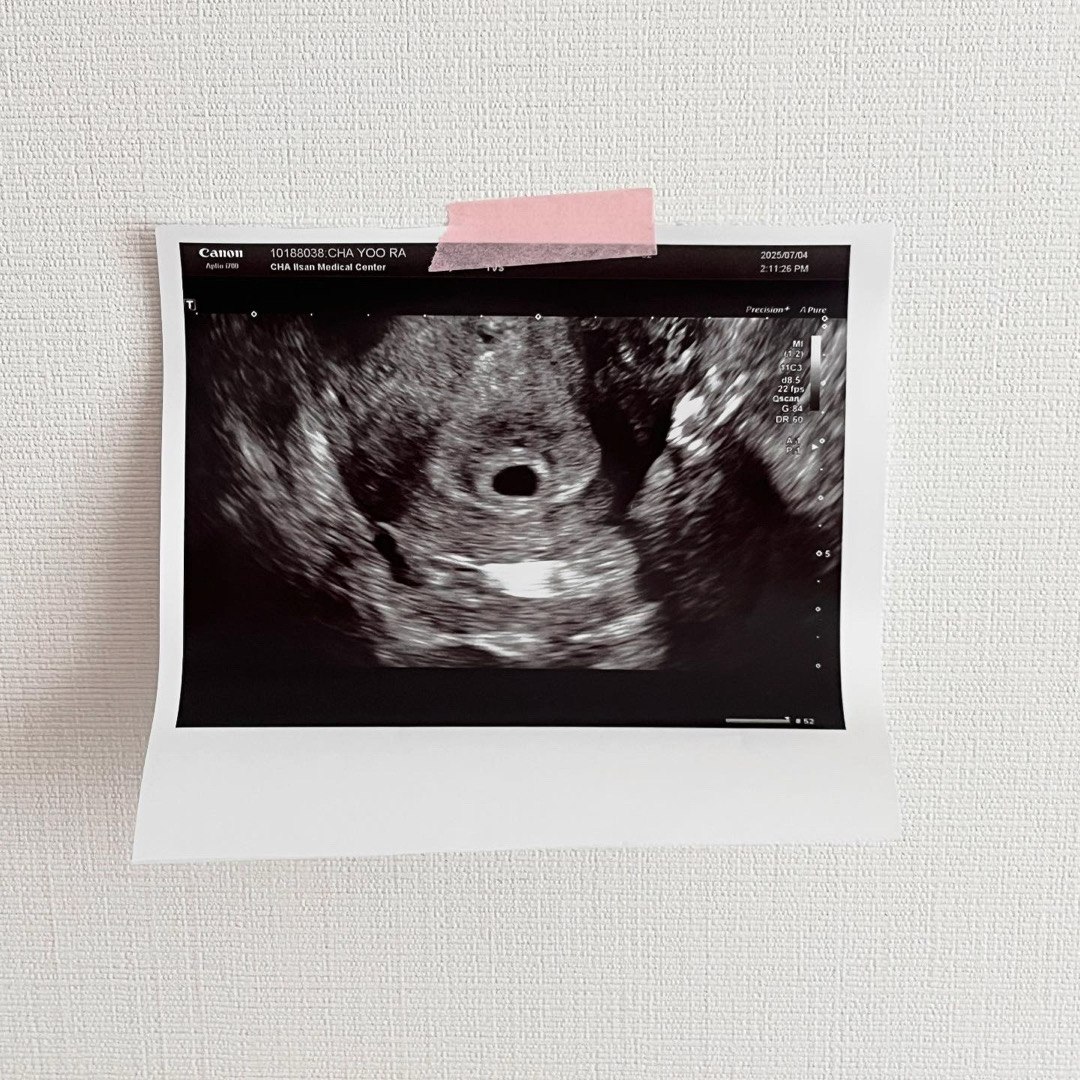

5주2일차 아기집 보고 왔어요!

난황도 볼 수 있을까 기대했는데 확대했을때 난황추정으로 보이는 부분이 있고 확실하게 보이진 않아서 아기집만 보고 왔어요! 이제 10일 후에 오라고 하셨는데 어떻게 기다리나요🥹